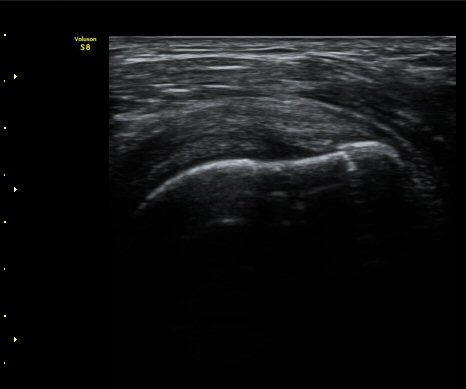

¼ºº° / ³ªÀÌ

¿©ÀÚ/ 50¼¼

ÁÖÁõ»ó

³Ñ¾îÁø ÈÄ ½ÉÇØÁö´Â ¾î±úÀÇ ÅëÁõ°ú °­Á÷

º´·Â

³Ñ¾îÁø ÈÄ ¾î±úÀÇ ÅëÁõÀÌ ¹ß»ýÇÏ¿© Ÿ º´¿ø ³»¿øÇÏ¿© ¿¢½º·¹ÀÌ °Ë»ç¿¡¼­ ƯÀÌ ¼Ò°ß ¾ø´Ù´Â ¼Ò°ßÀ» µè°í Áö³ÁÀ¸³ª ¾î±úÀÇ ÅëÁõÀÌ ½ÉÇØÁö°í Á¡Á¡ ¾î±ú°¡ ±»¾îÁ® ³»¿ø

ÃÊÀ½ÆÄ °Ë»ç